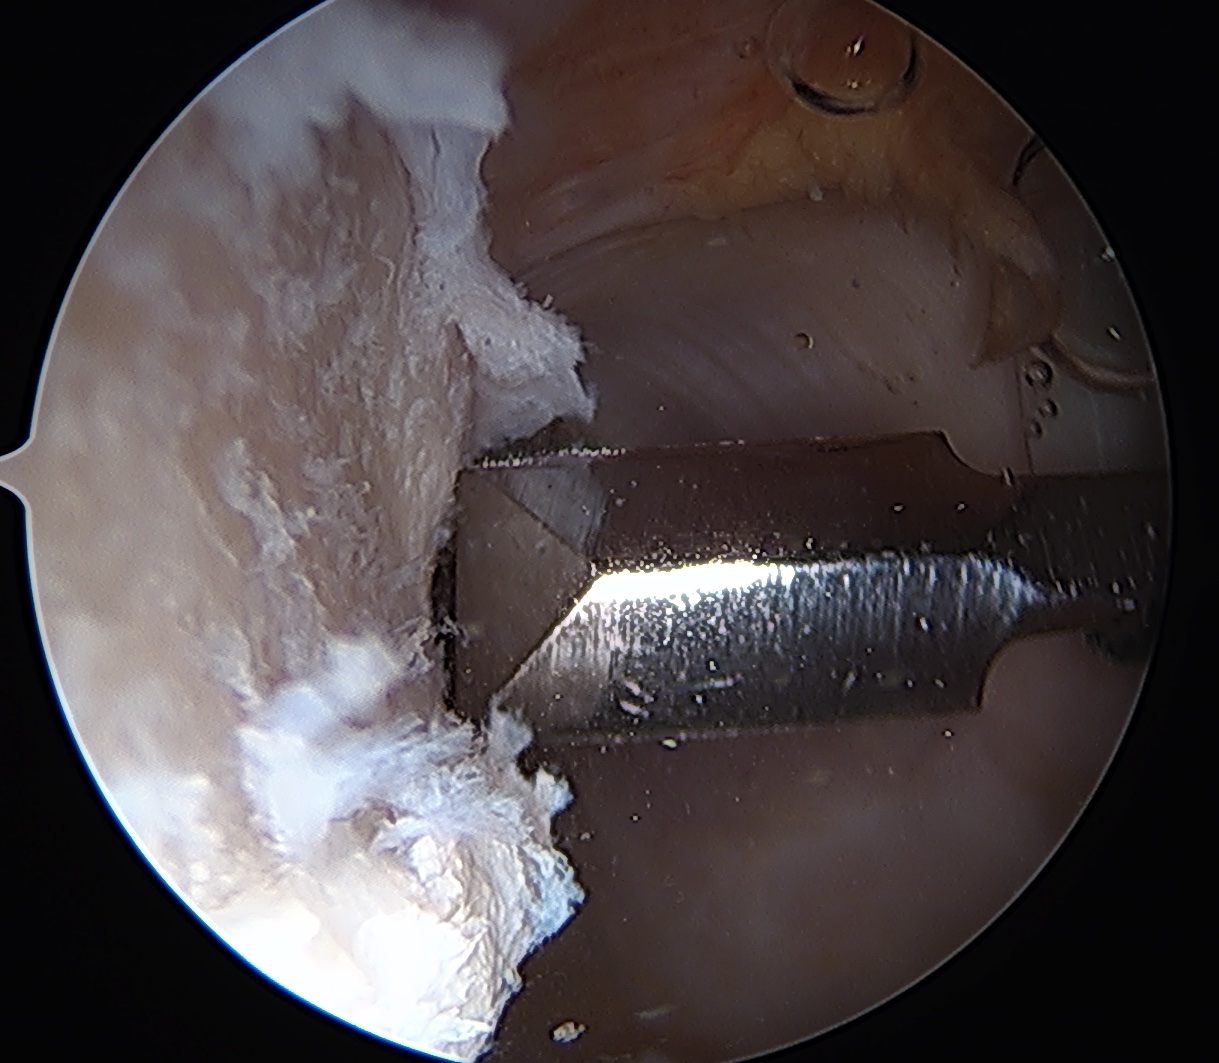

End result

Filling Hill Sachs defect with infraspinatus / posterior capsule